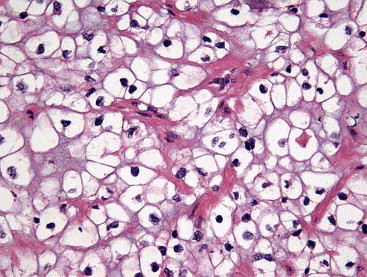

65 y/o man with painless hematuria. Renal Biopsy is preformed. What is the likely etiology and what makes up these cells?

Clear Cell Carcinoma - most common renal malignancy

Cells made up of glycogen and lipid accumulation